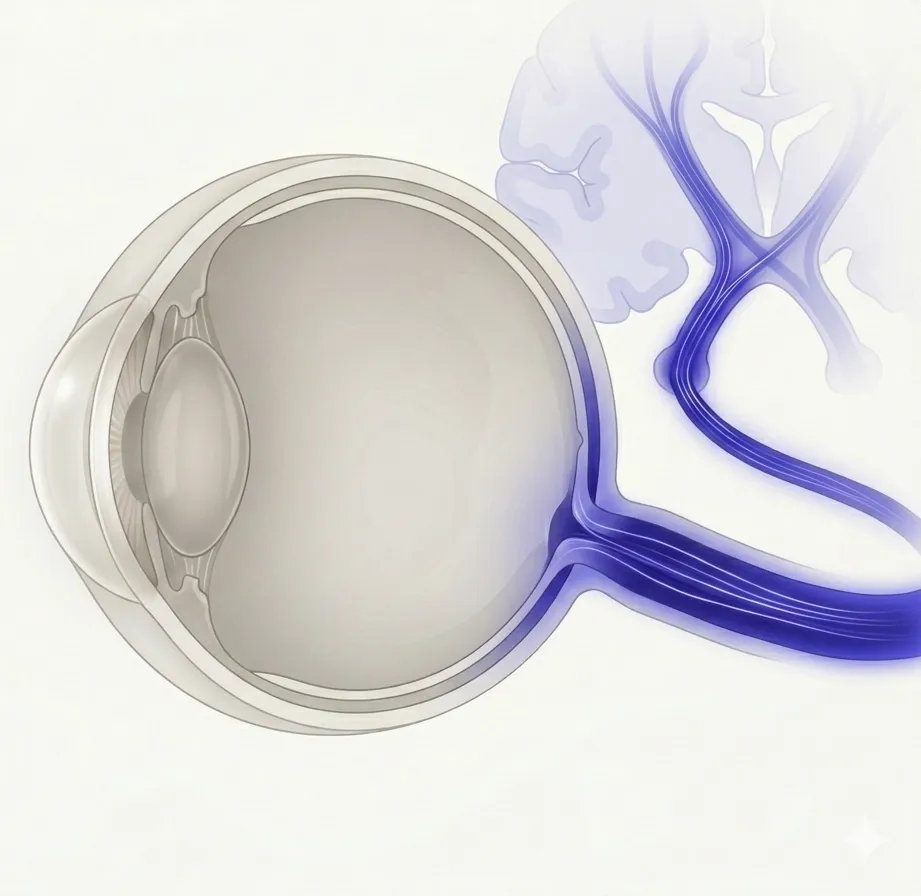

眼は脳や神経系と密接に結びついており、視神経・動眼神経・瞳孔に関わる神経経路の異常がさまざまな眼の症状として現れます。このカテゴリでは、視神経の炎症・眼球運動の障害・瞳孔の異常など、神経系の病変に由来する眼の疾患を扱います。